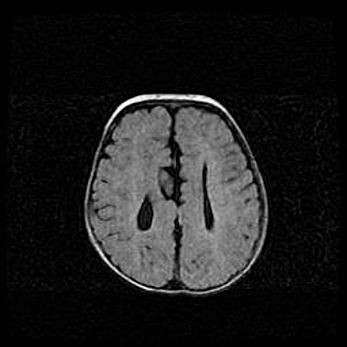

Сообщающаяся гидроцефалия. Кистозная энцефаломаляция головного мозга.

Возраст: 3 месяца 4 дня

Вес: 3100 г

Пол: женский

Окружность головы: 34 см

Срок гестации: 31 неделя

Кистозная энцефаломаляция головного мозга - одна из форм поражения головного мозга в детском возрасте. Характеризуется возникновением множественных и распространённых кист в коре, белом веществе и подкорковых образованиях головного мозга у плодов, новорождённых и детей раннего возраста. Развитие кистозной энцефаломаляции связано с внутриутробной асфиксией и гипотонией, родовой травмой, тромбозом синусов, пороками развития сосудов, инфекциями, сепсисом и другими причинами. Наиболее значимые инфекционные агенты: вирусы простого герпеса, цитомегалии, краснухи, токсоплазмы, энтеробактерии, золотистый стафилококк и другие.